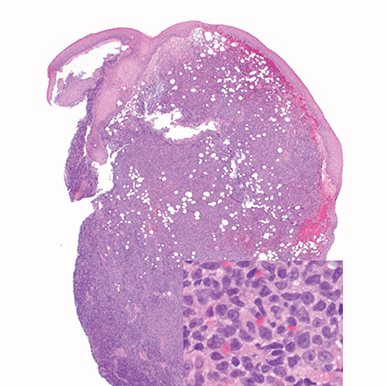

Skin

Punch biopsy of a skin lesion showing BPDCN (H&E stain, x40) and (inset) medium-sized malignant cells spare the epidermis (H&E stain, x1000).11

BPDCN with low-density infiltrate may mimic an inflammatory condition4

BPDCN with low-density infiltrate BPDCN with low-density infiltrate

• Cutaneous cases with minimal involvement show periadnexal and perivascular infiltrate, clustering in the superficial to mid dermis12,13

• Cytology, in association with flow cytometry immunophenotyping and clinical history, can help obtain an accurate diagnosis of BPDCN14

H&E, hematoxylin and eosin.